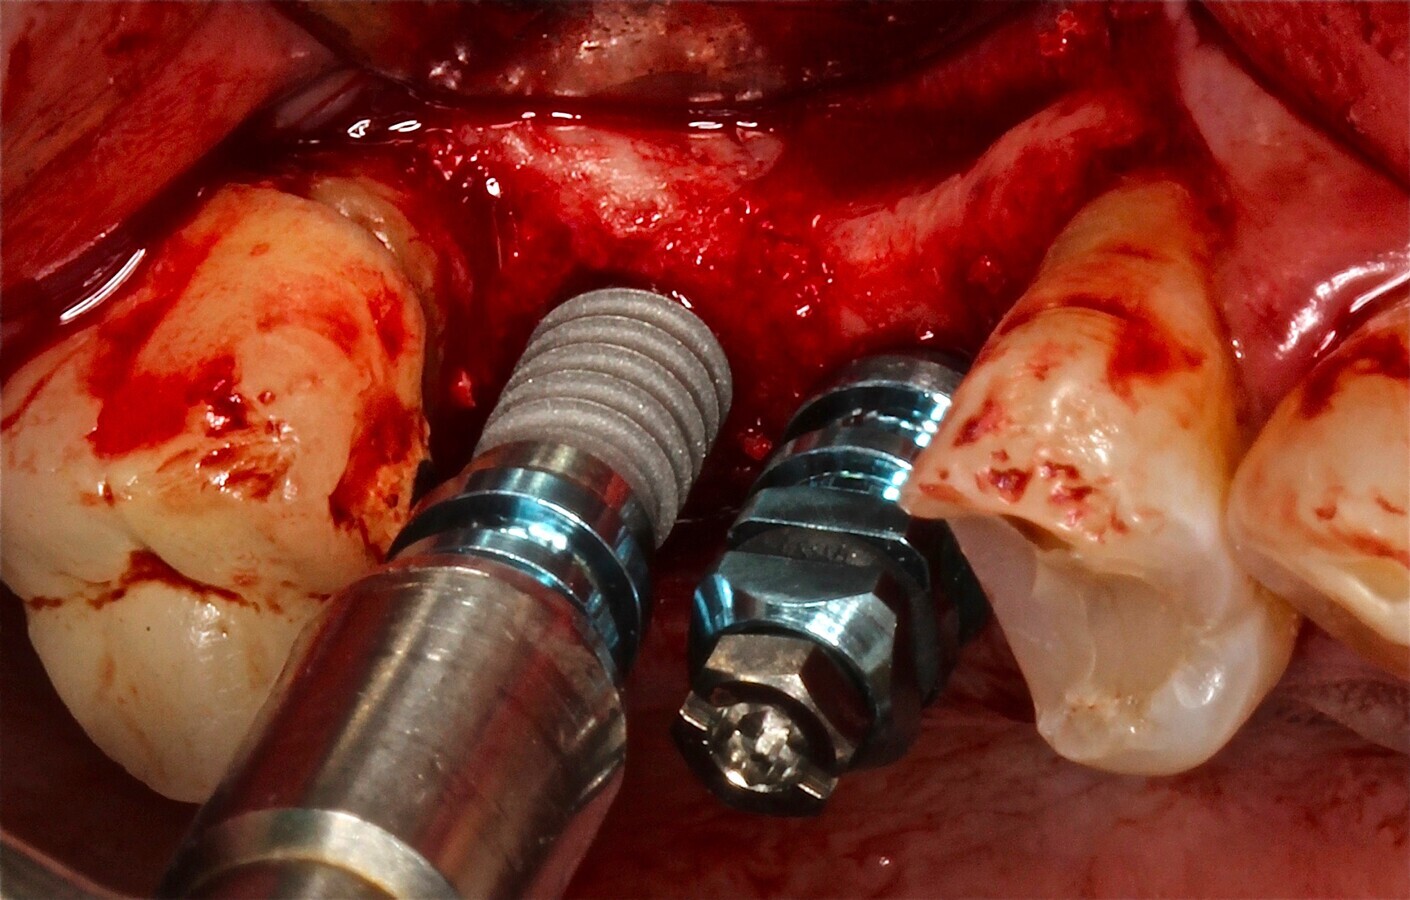

Fig. 10 Figura 10

1. Inserción del implante, con una estabilidad primaria correcta y posición prostodóntica ideal.

2. Realización de perforaciones en el lecho con fresa redonda para aumentar la disponibilidad de células osteogénicas y acelerar la revascularización y mejorar la unión injerto huésped.